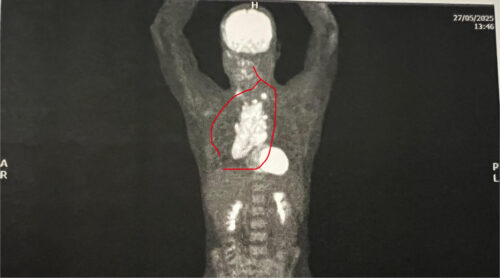

As time passed, the symptoms worsened. Travis began struggling to breathe, and his neck and jugular vein swelled. This led to a CT scan that finally revealed “multiple swollen lymph nodes.” An urgent follow-up CT scan with contrast on his chest prompted a call within 1.25 hours, instructing him to return to his GP immediately and to bring his mother. “I had never thought there was anything wrong with my chest,” he admits, despite some minor tenderness around the collarbone.

The following day, 22nd May 2025, Travis and his mother met with his GP. It was then that he learned about the mass growing in his chest: “It was explained that it was indicative and highly probable to be Lymphoma or some other form of cancer.” That same day, Travis was supported and triaged through the emergency department at Box Hill Hospital and the following day admitted into the cancer ward where a biopsy confirmed Classical Hodgkin Lymphoma Stage 2b. Travis remained at the ward for 2 weeks. The size of his ‘bulky disease’ was 14cm x 8cm x 6cm.